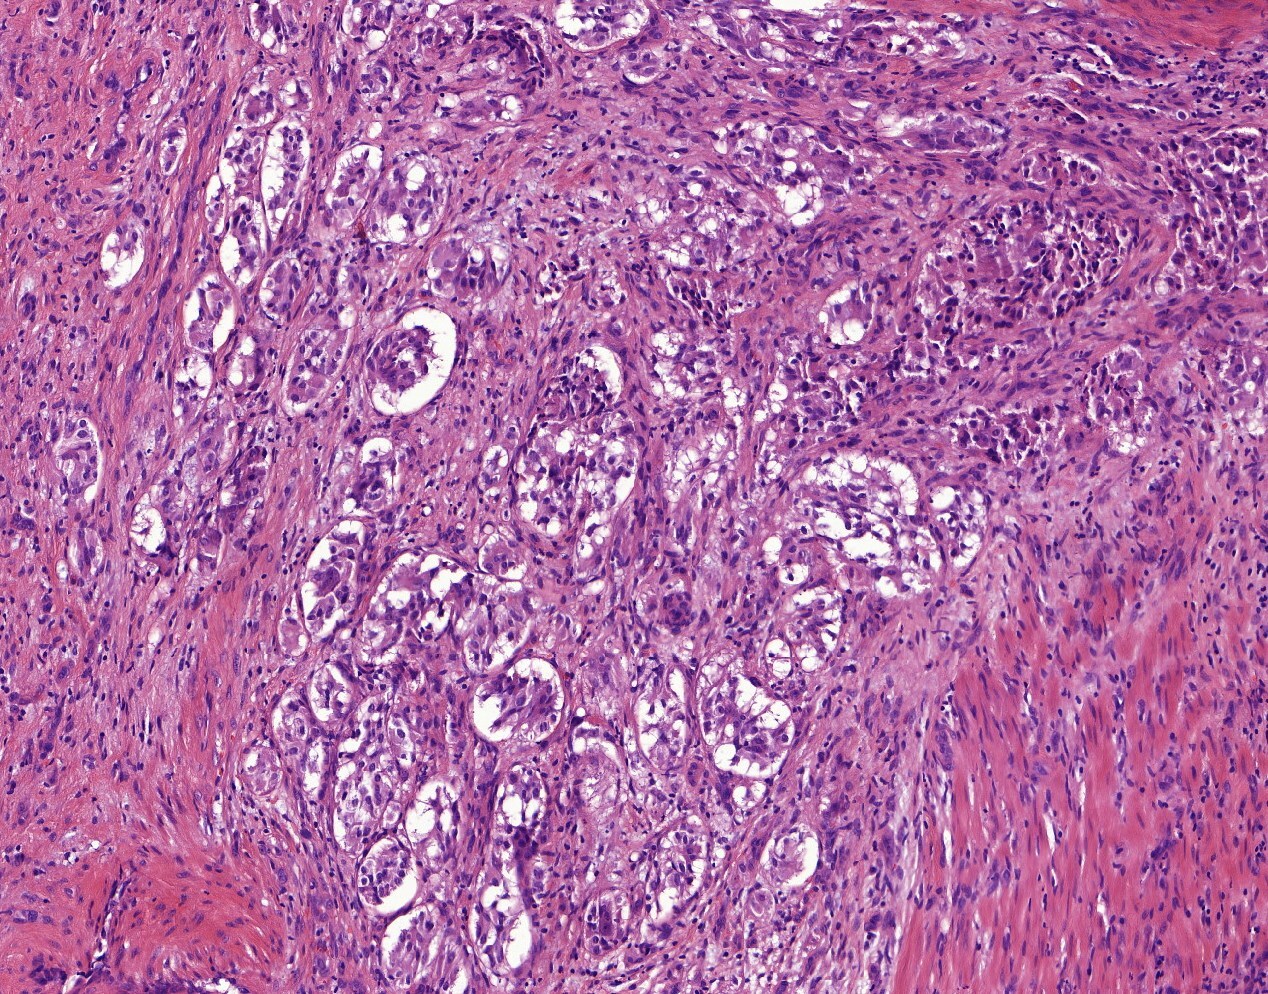

12

Q

colonic mass

Dx?

IHC?

Micropapillary carcinoma

IHC: MUC1 (EMA) inside-out staining